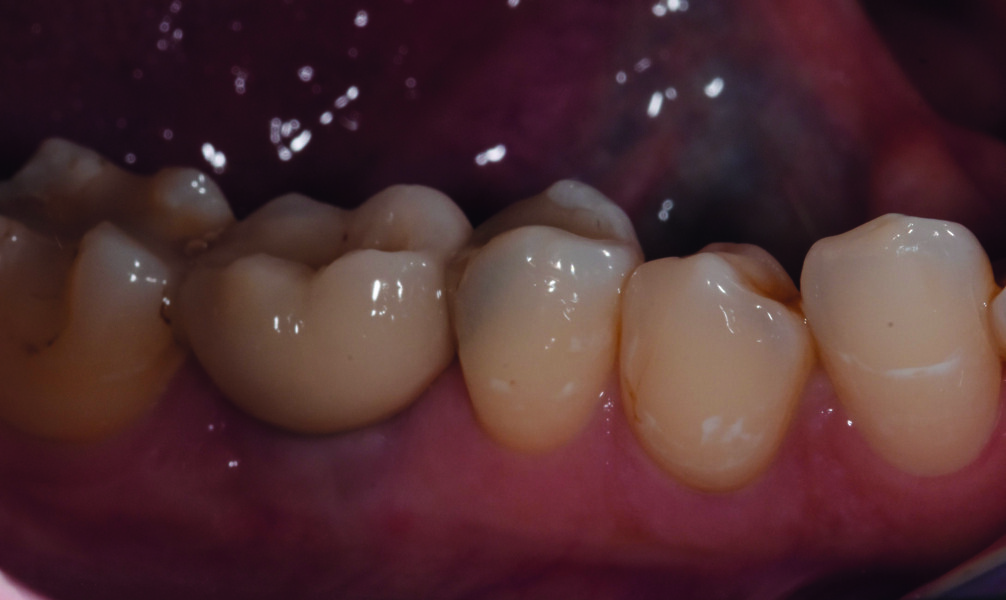

Jour de la pose de la couronne d’usage

Fig. 26 : Intégration de la couronne d’usage, avec vérification de l’occlusion, en vue vestibulaire.

Fig. 27 : Intégration de la couronne d’usage, en vue occlusale.